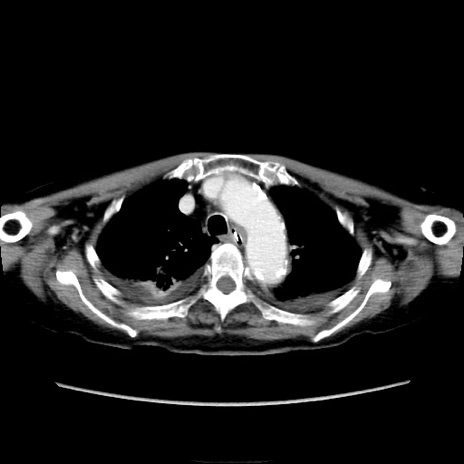

症例40(横断像)

他院CT

横断像